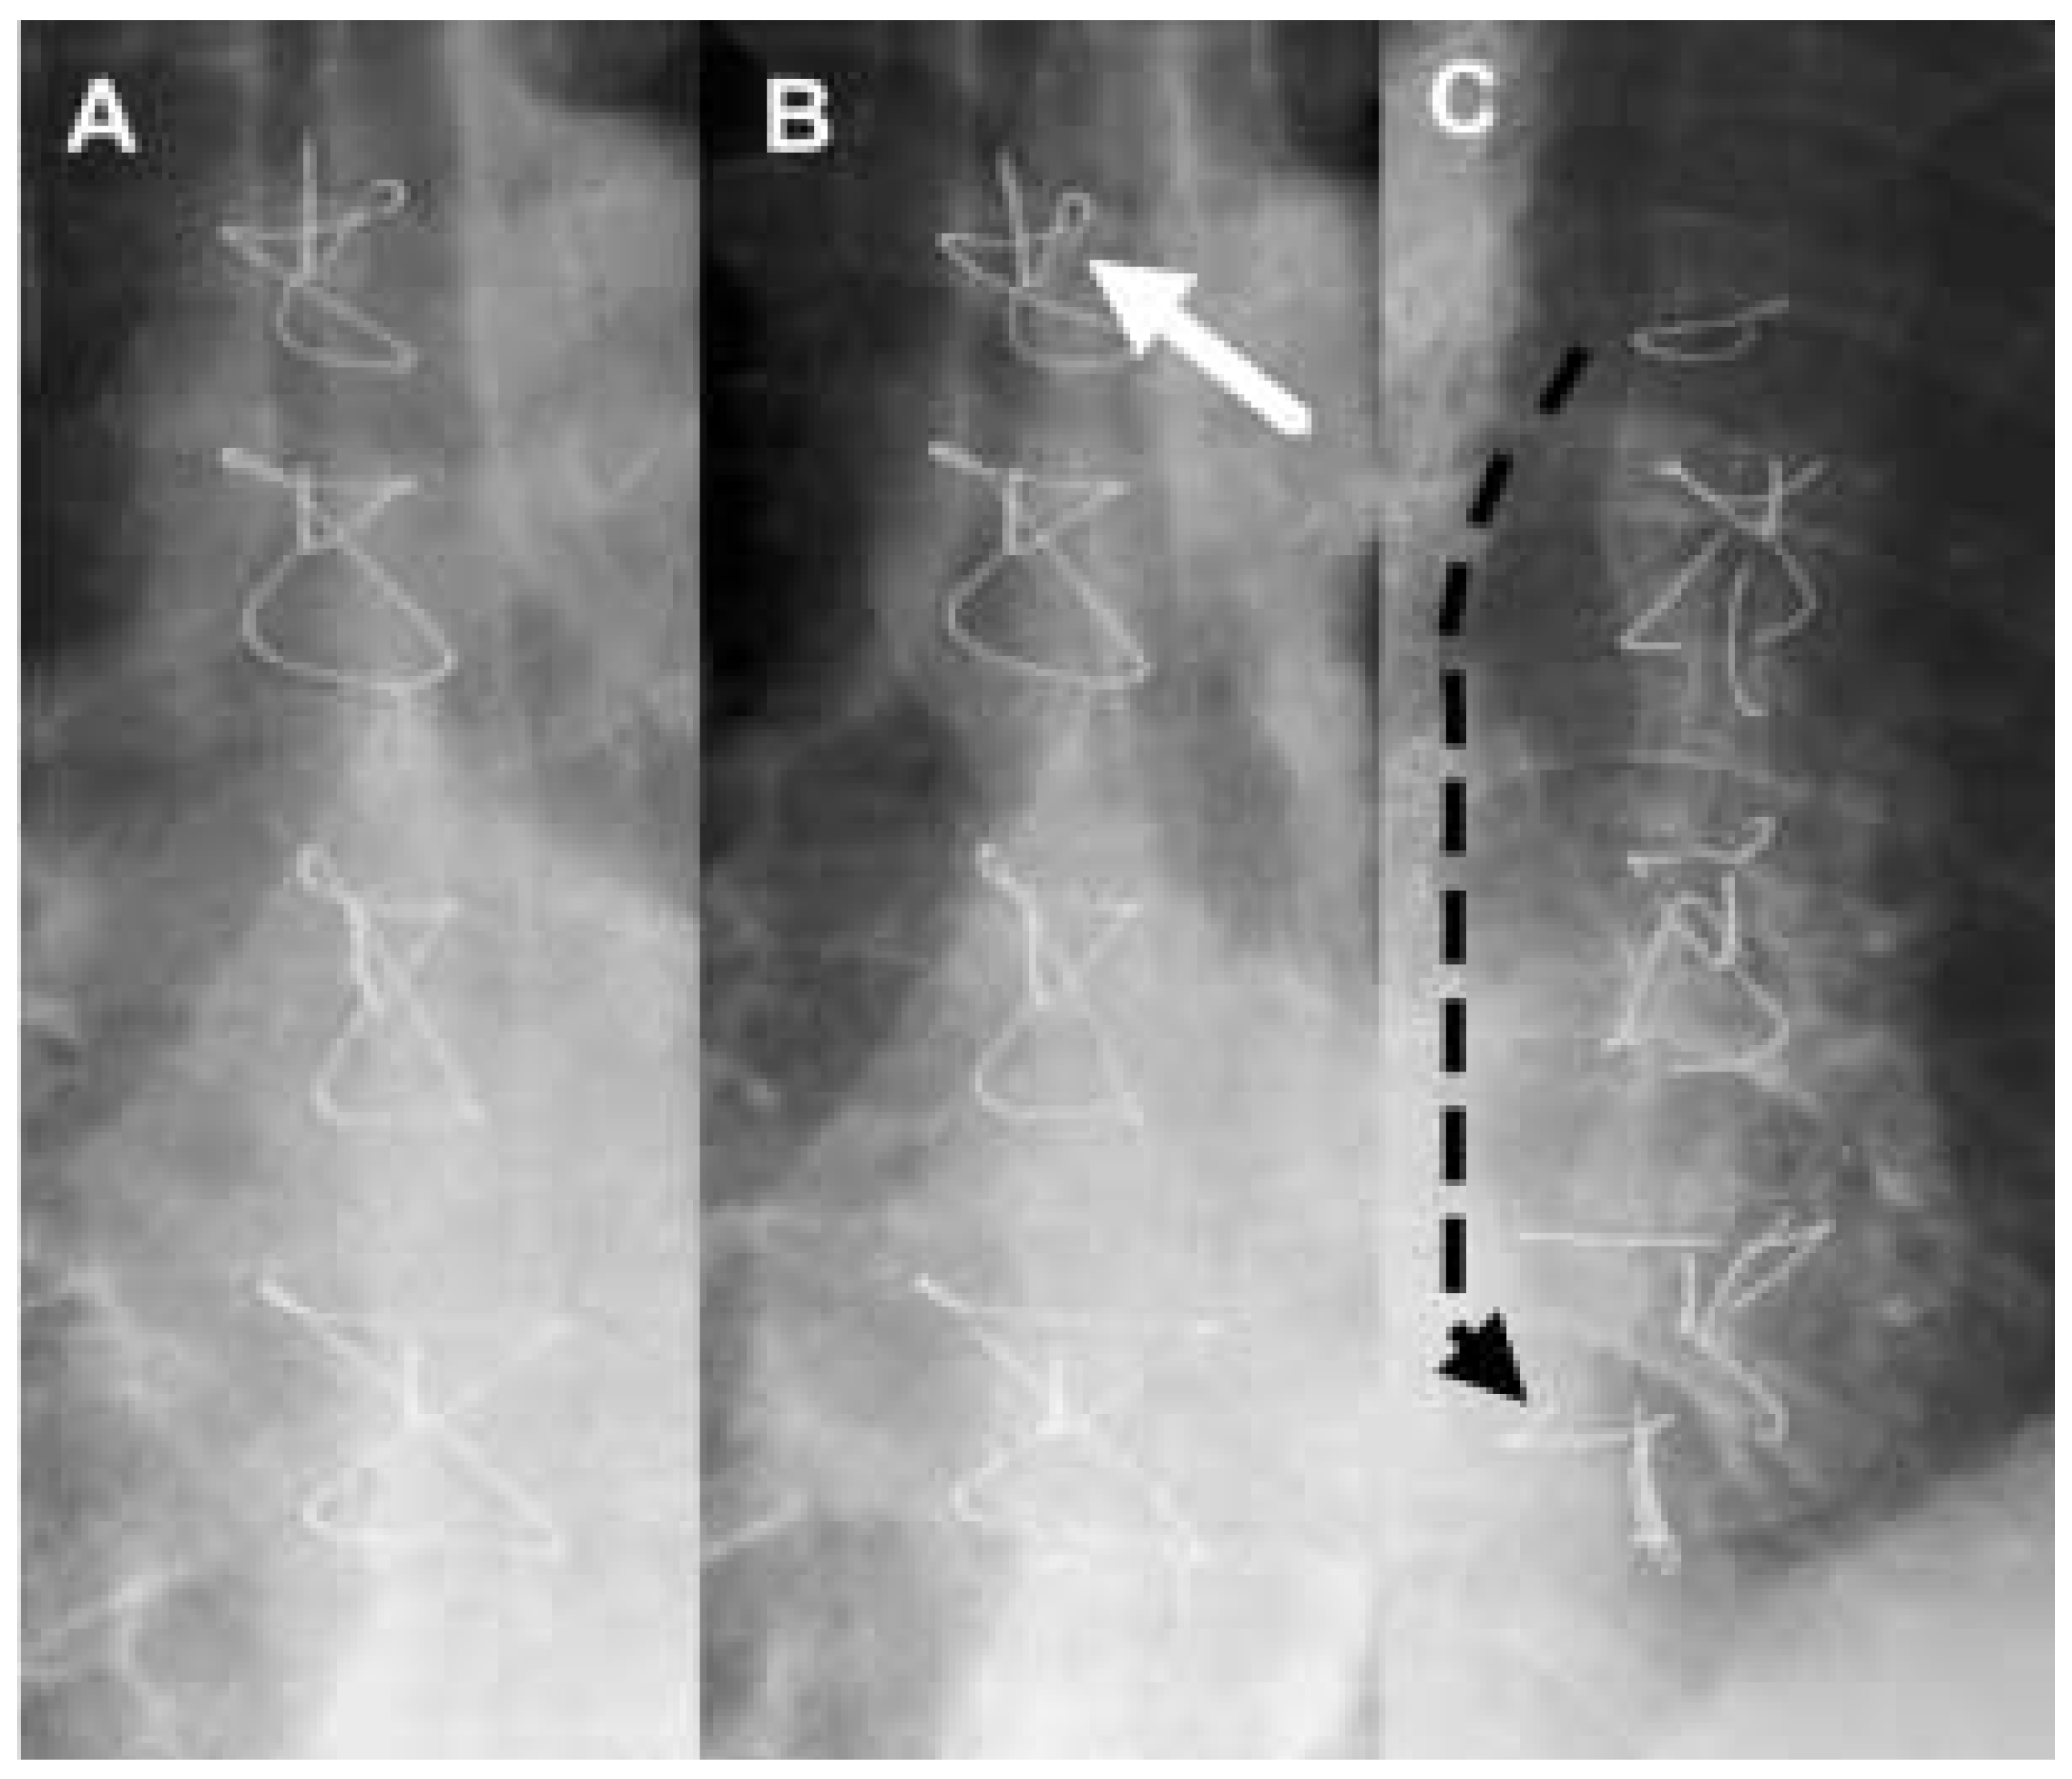

A 74-year-old white male smoker with chronic obstructive pulmonary disease and marked coughing experienced a transmural, anterior myocardial infarction two years prior to the current visit. Because of postinfarction angina, he underwent elective coronary artery bypass grafting including the use of the left internal mammary artery at our institution (Figure 1a). His postoperative course was complicated by persistent smoking and coughing. Three months after operation, he presented to our outpatient clinic with cough-induced pain at the proximal end of the sternum. The thoracic X-ray showed fracture of the proximal sternal wire (Figure 1b). One and a half year later, the patient presented again with pain on coughing and moving, now expanding all over his sternum. He experienced no pain with normal breathing. His physical examination revealed a median thoracic scar without signs of inflammation nor palpable wires, but abnormal sternal mobility with cracking. The thoracic X-ray showed fracture of all sternal wires (Figure 1c). In addition, fractured parts of the proximal wire have migrated at the dorsal side of the sternum from its proximal to its distal end. Aconservative management with regular controls was chosen given the minor complaints of the patient. The decision against reoperation based on the increased risk of injuring the bypasses (in particular the mammary graft to the left anterior descending coronary artery), the likelihood of postoperative infection as well as recurrence of postoperative pseudoarthrosis given the patients ongoing smoking and coughing.

Figure 1. Series of conventional X-rays of sternum: (A). Shortly after coronary artery bypass operation; note the intact sternal wires. (B). Three months post surgery; breaking of the proximal sternal wire (white arrow) caused by coughing. (C). 112 years later; complete breaking of all sternal wires and distal migration of wire particles (black arrow) causing pain on coughing and movements of the patient.